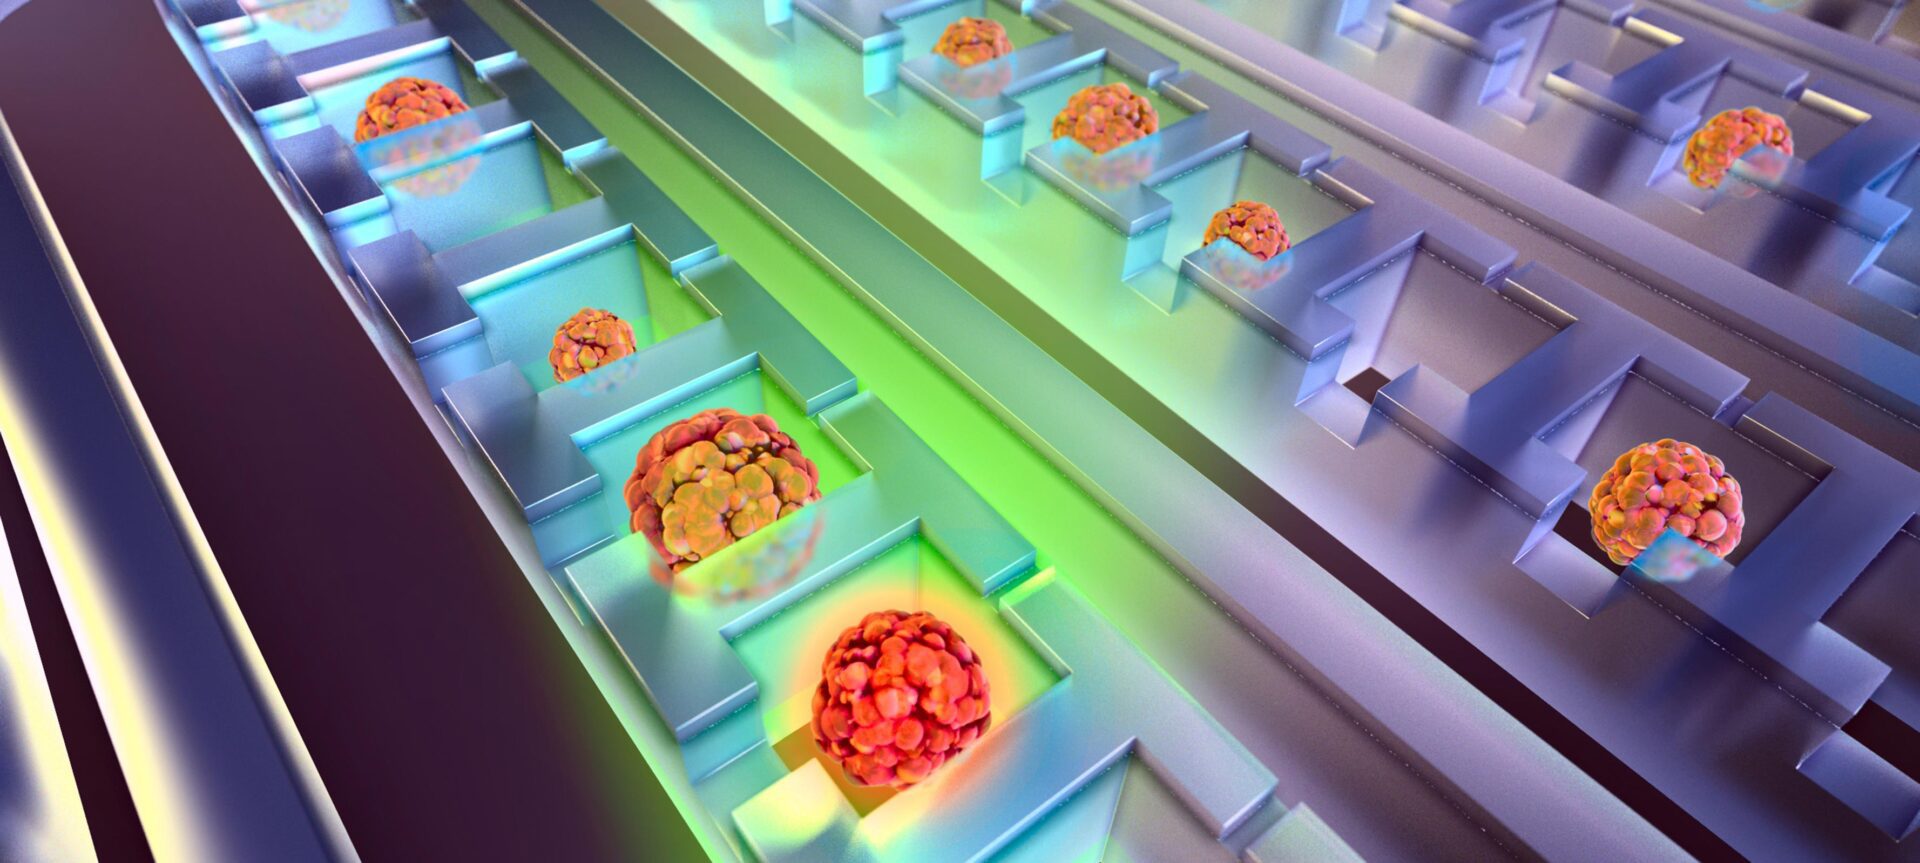

Is lung cancer treatment working? This chip can tell from a blood draw

By trapping and concentrating tiny numbers of cancer cells from blood samples, the device can identify whether a treatment is working at the four-week mark.

Cancer stem cells: new method analyzes 10,000 cells at once

A new tool for making sense of the cells believed to cause cancer relapses and metastases.

Michigan engineers release individual cells from a specially-designed chip using laser pulses.

Capturing cancer cells from blood samples offers a non-invasive way to observe whether the cancer is disappearing or whether it is becoming resistant to the treatment.

Prof. Euisik Yoon and his team developed a new machine learning tool that enables large-scale testing of cancer drug effectiveness with microfluidics.

To improve the prediction and identification of stem-like cancer cells, Prof. Euisik Yoon’s group developed a method that is 3.5 times faster than the standard approach.